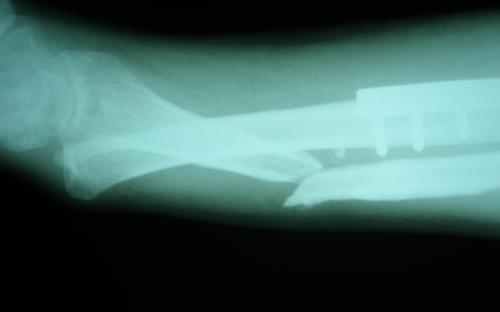

Άντρας 21 ετών υπέστη διπολικό κάταγμα της κερκίδας και κάταγμα της ωλένης, που αντιμετωπίστηκε σε περιφεριακό νοσοκομείο. 9 μήνες μετά διαπιστώθηκε ψευδάρθρωση της κερκίδας με οστικό απόλυμα 6,5 εκ. Αντιμετωπίστηκε με τη χρήση αγγειούμενης περόνης, η οποία γεφύρωσε το οστικό έλλειμμα της κερκίδας.